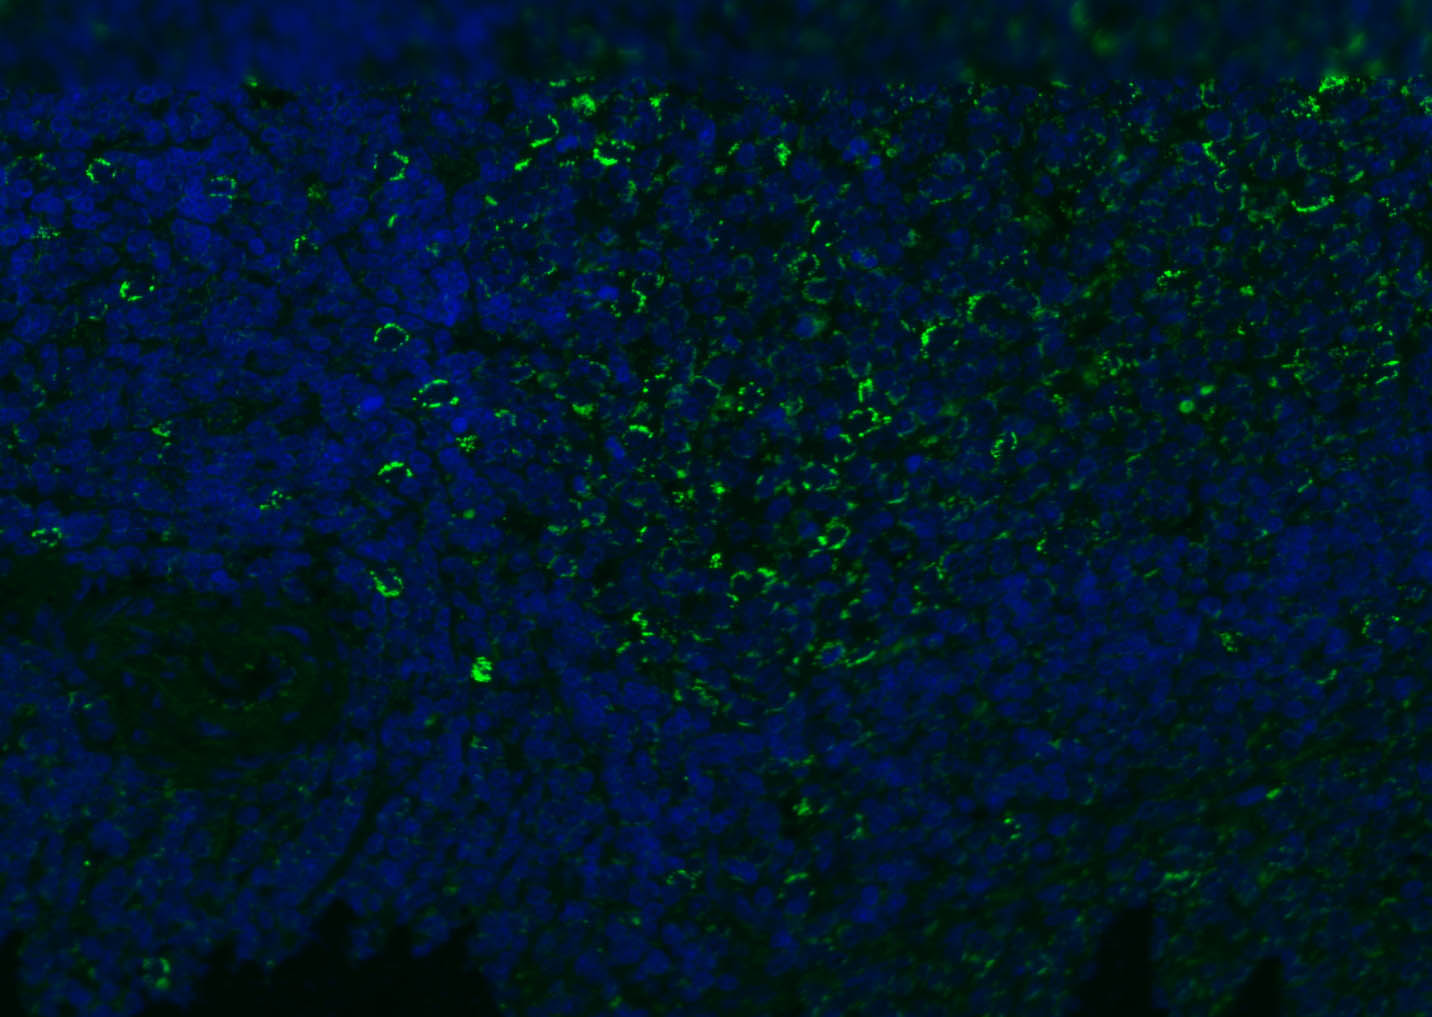

Paraformaldehyde-fixed, paraffin embedded (human tonsil); Antigen retrieval by boiling in sodium citrate buffer (pH6.0) for 15min; Blocking buffer (normal goat serum) at 37°C for 30min; Antibody incubation with (CD8B) Polyclonal Antibody, Unconjugated (bs-4914R) at 1:200 overnight at 4°C, followed by a conjugated Goat Anti-Rabbit IgG antibody (bs-0295G-FITC) for 90 minutes, and DAPI for nuclei staining.